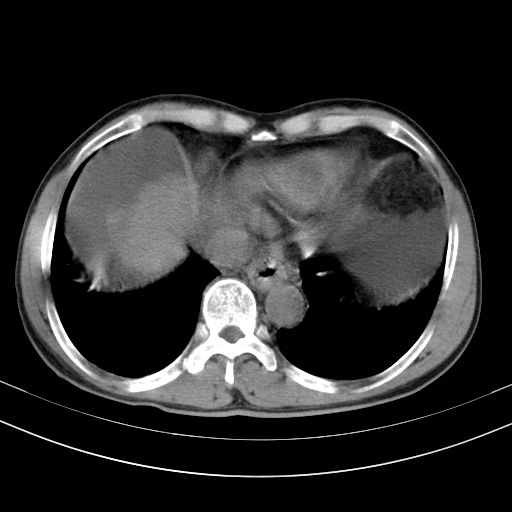

以下是引用随光逐影在2010-2-28 10:23:00的发言:[br]1)考虑肝癌;建议行ct增强扫描检查。2)肝硬化,脾大,腹水。3)慢性胆囊炎。